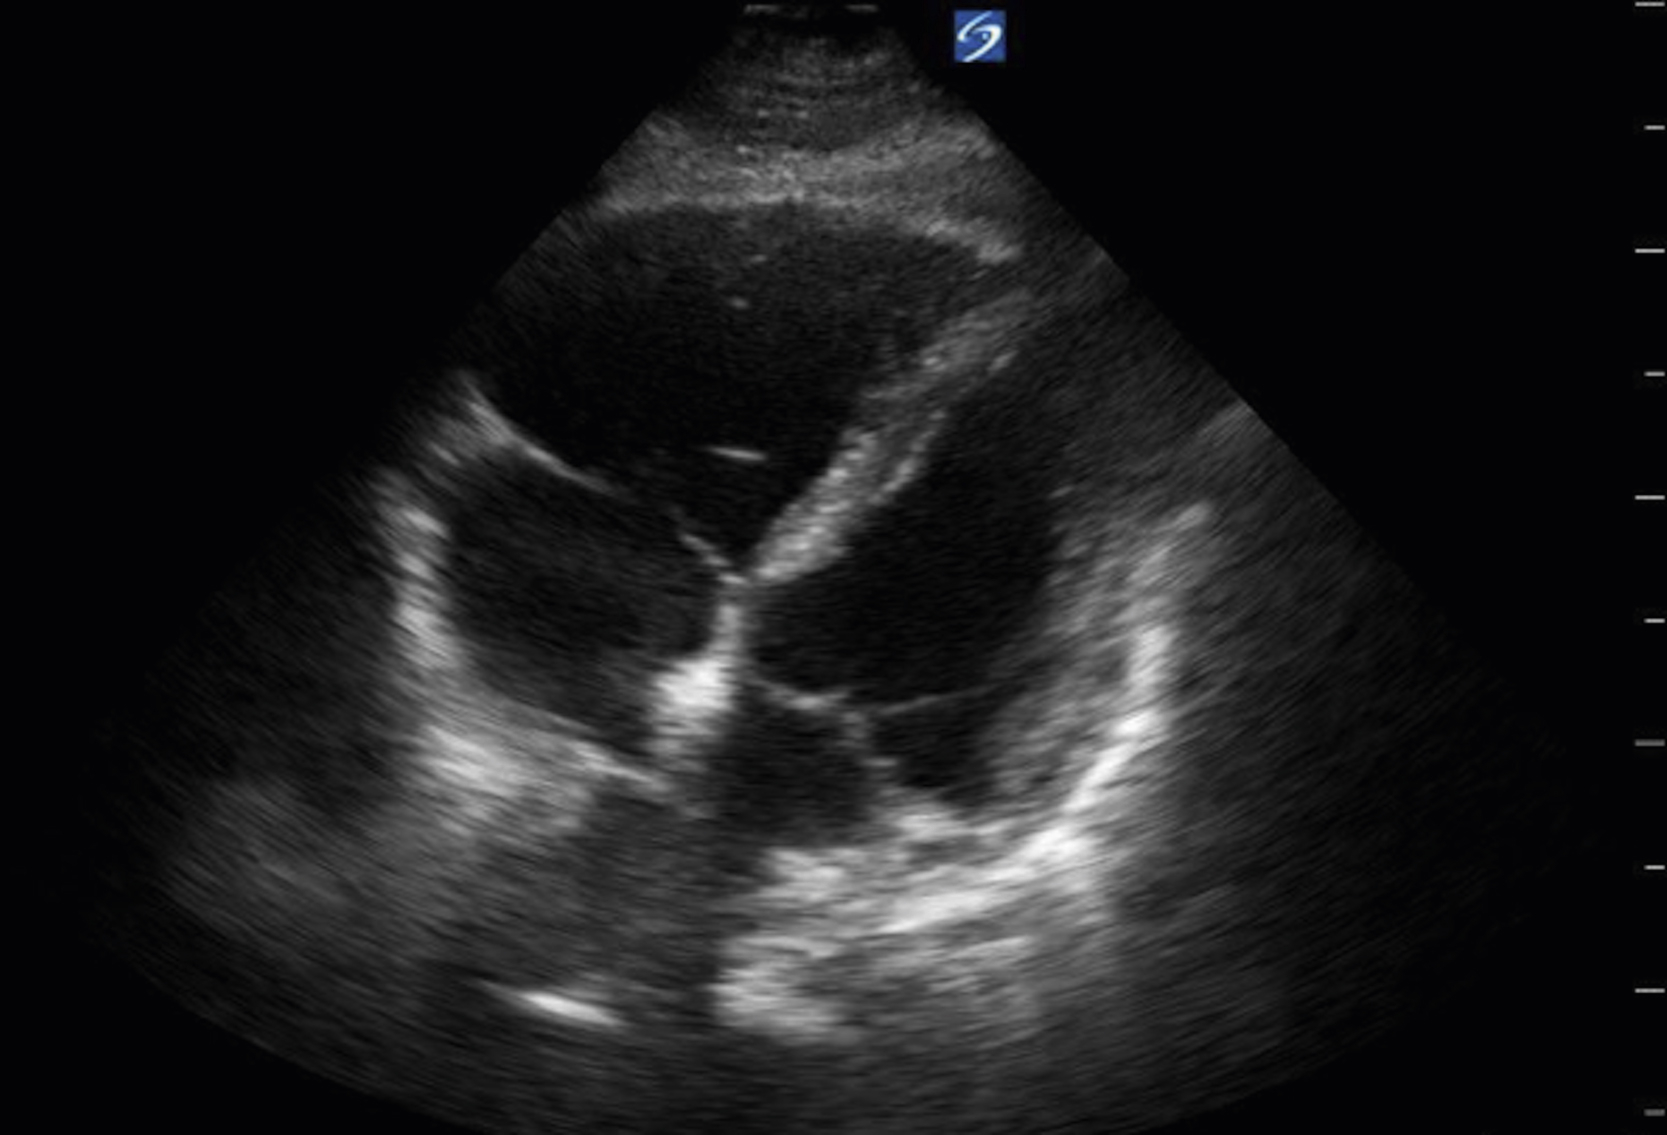

Image Acquisition

Cardiac US is performed through the transthoracic and transabdominal windows with the use of small curvilinear or phased array transducers. Typical views include the subcostal four-chamber view (subxiphoid), parasternal long-axis view ( Fig. e3.10 ; see Video e3.4 ), parasternal short-axis view, and apical four-chamber view. The subcostal four-chamber view, as in the FAST, is ideal for assessment of pericardial effusion and useful during cardiac arrest because it does not interfere with chest compressions. The long-axis subcostal view highlights the inferior vena cava (IVC) and can indicate volume status. The parasternal views are excellent windows for LV assessment. The apical four-chamber view is ideal for comparison of RV and LV sizes and function. Several US protocols have been developed to evaluate undifferentiated hypotension and can be used to narrow the differential diagnosis.

Normal parasternal long-axis view of the heart.